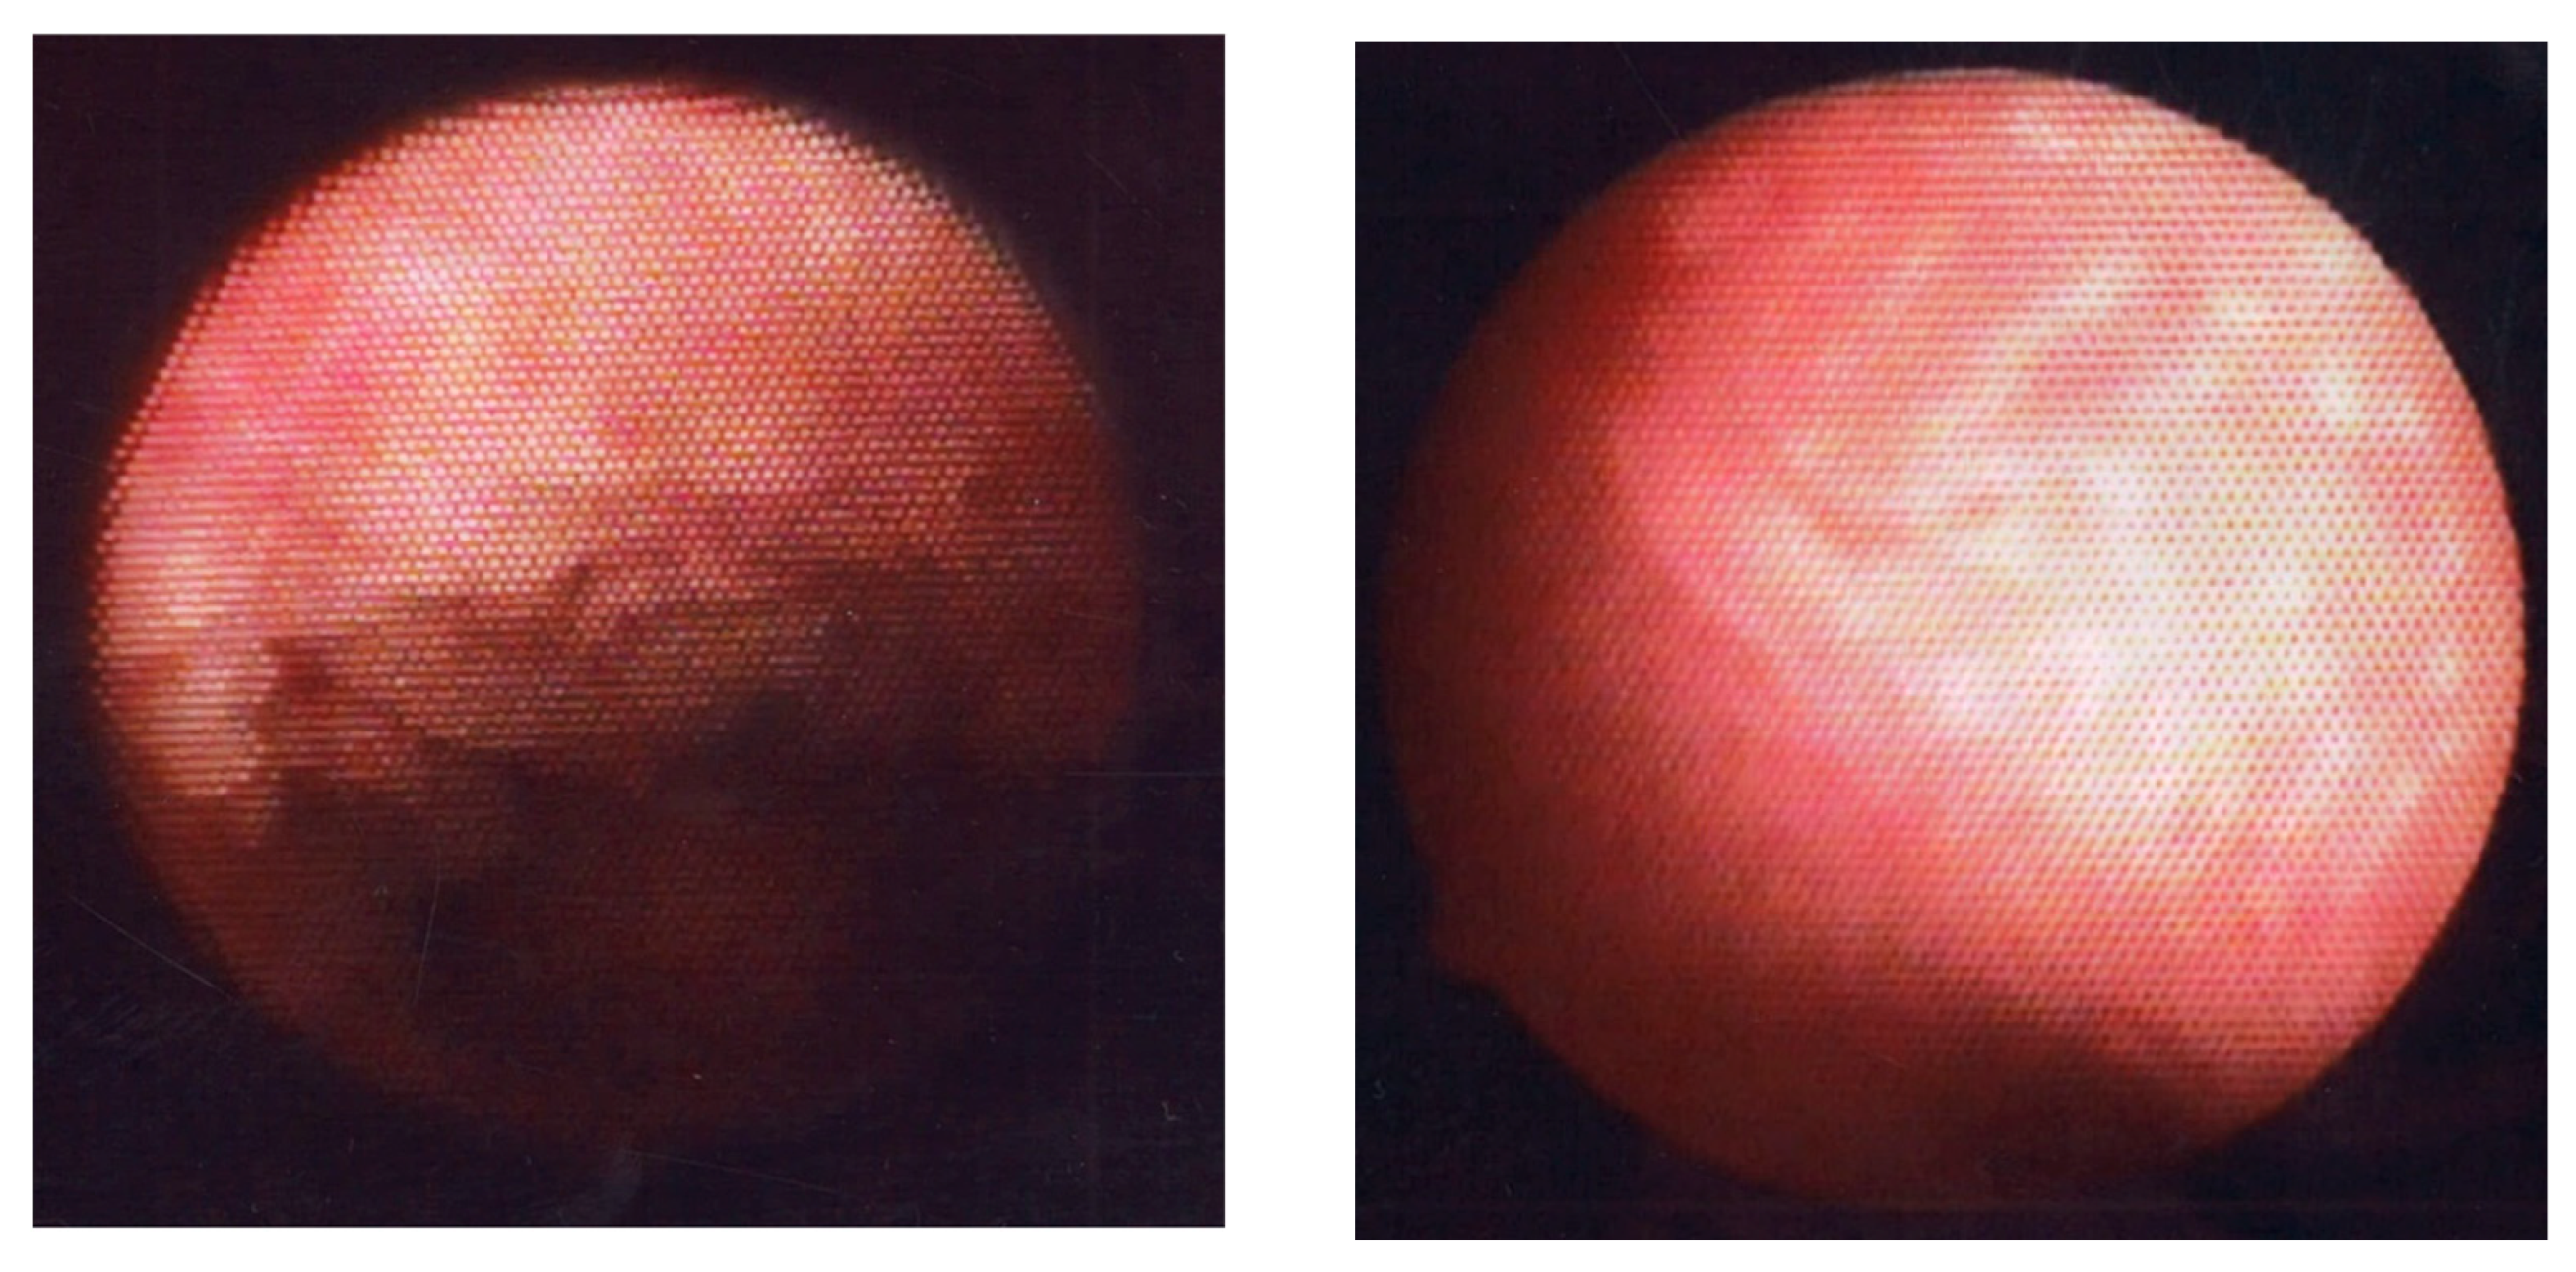

- Cicinelli, E.; Resta, L.; Nicoletti, R.; Zappimbulso, V.; Tartagni, M.; Saliani, N. Endometrial Micropolyps at Fluid Hysteroscopy Suggest the Existence of Chronic Endometritis. Hum. Reprod. 2005, 20, 1386–1389. [Google Scholar] [CrossRef] [PubMed]

- Song, D.; Li, T.C.; Zhang, Y.; Feng, X.; Xia, E.; Huang, X.; Xiao, Y. Correlation between hysteroscopy findings and chronic endometritis. Fertil. Steril. 2019, 11, 772–779. [Google Scholar] [CrossRef] [PubMed]

- Kitaya, K.; Yasuo, T.; Yamaguchi, T.; Morita, Y.; Hamazaki, A.; Murayama, S.; Mihara, T.; Mihara, M. Construction of Deep Learning-based Convolutional Neural Network Model for Automatic Detection of Fluid Hysteroscopic Endometrial Micropolyps in Infertile Women with Chronic Endometritis. Eur. J. Obstet. Gynecol. Reprod. Biol. 2024, 297, 249–253. [Google Scholar] [CrossRef]